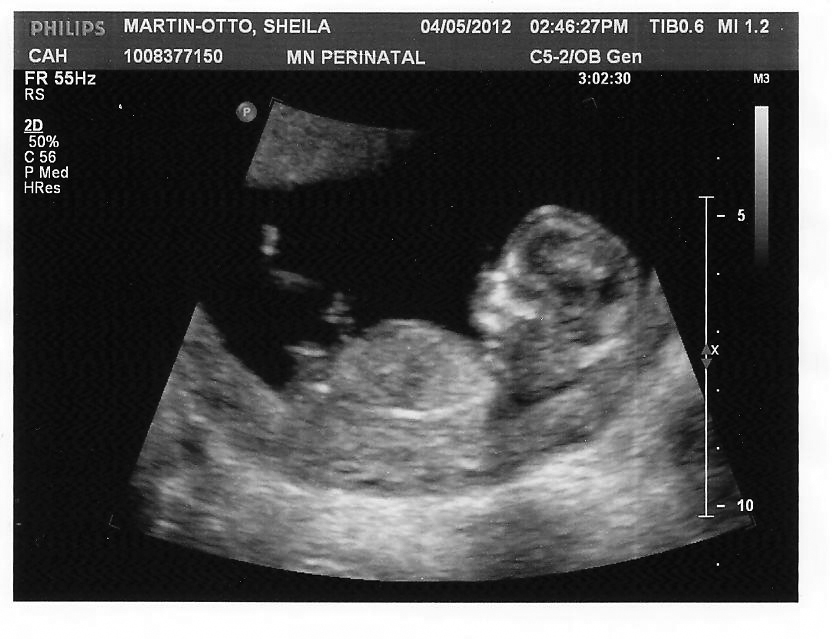

***EDIT!!! This top pic is one I just found with my huge batch of u/s pictures! Is that a proper nub-shot??

Attachment 1943